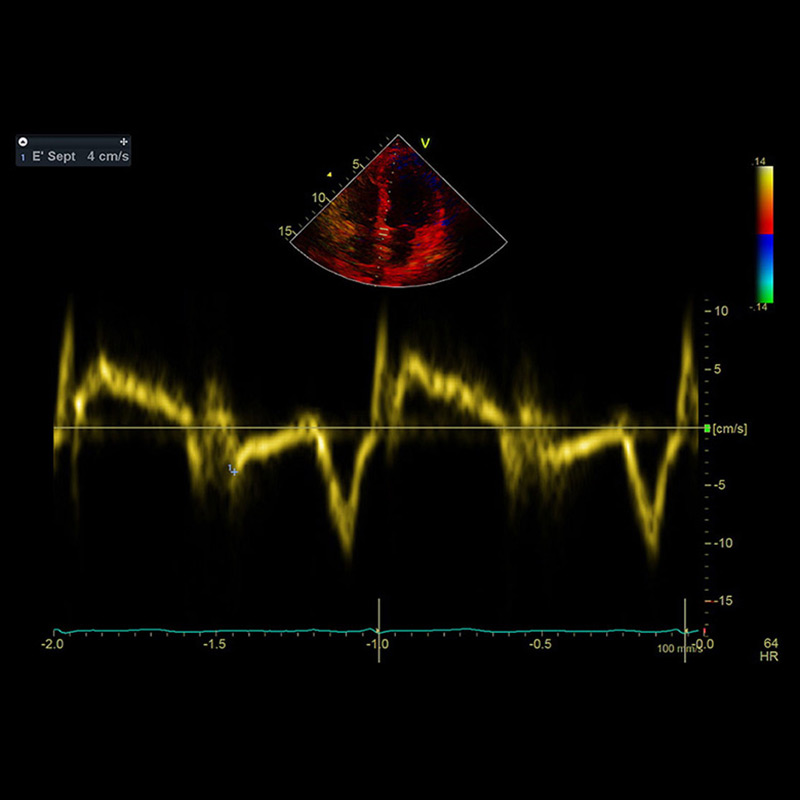

Im Echo beurteilen wir den strukturellen Zustand des Myokards (Herzmuskels), der Herzklappen und des Herzbeutels. Die besondere Domäne der Echokardiographie ist aber die Beurteilung der Funktion von Herzmuskel und Herzklappen. Sie ist damit das wichtigste Instrument zur Diagnostik von Herzinsuffizienz (Herzschwäche) oder Klappenerkrankungen.